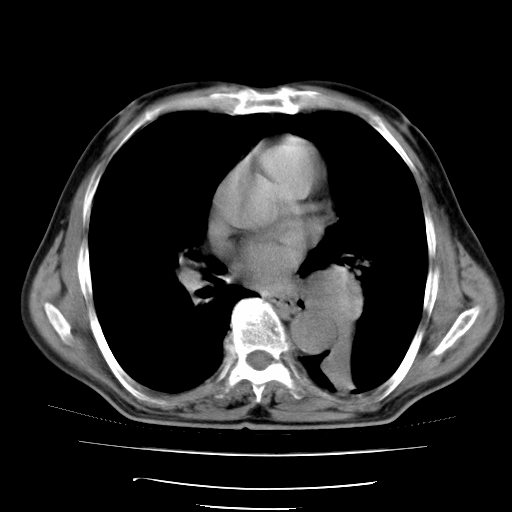

男,71岁,咳嗽,气喘10年,再发并咯血.胸片见气胸

考虑  左肺中心型肺癌伴阻塞性肺炎,肺不张,纵膈淋巴结肿大。慢支炎,肺气肿,左侧气胸肺压缩5%

左侧中央型肺癌伴纵膈淋巴结转移。

左肺中心型肺癌伴阻塞性肺炎,肺不张,纵膈淋巴结肿大

1)考虑左肺中心型肺癌伴阻塞性肺炎、左肺下叶肺不张、左侧肺气肿,纵膈淋巴结转移。2)左侧气胸(肺组织压缩约5%)。

左肺中心型肺癌伴阻塞性肺不张、肺气肿 。

1)考虑左肺中心型肺癌伴阻塞性肺炎、左肺下叶肺不张、左侧肺气肿,纵膈淋巴结转移。2)左侧气胸。